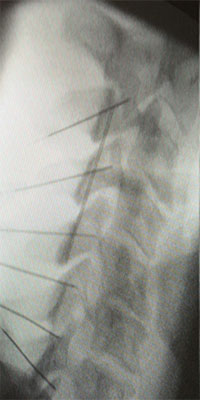

El procediment s’ha de realitzar en un quiròfan, per mantenir l’asepsia i garantir una precisió absoluta en la col·locació de la cànula, utilitzant control radiològic per visualitzar exactament la zona d’introducció.

La Radiofreqüència cervical es pot realitzar en totes les articulacions facetàries, com es mostra a la figura, en els nivells C4, C5, C6, C7 i T1.

L’objectiu del procediment és aplicar la radiofreqüència a la branca dorsal del nervi raquidi posterior, que és responsable de la innervació de l’articulació facetària.